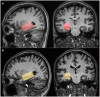

Methods: In this cross-sectional study, 20 patients with aMCI and 20 age- and gender-matched healthy controls (HCs) underwent MEGA Point Resolved Spectroscopy (MEGA-PRESS) and APTw MR imaging at 3 T. GABA+, Glx, and APTw signals were measured in the right hippocampus. The GABA+ levels, Glx levels, Glx/GABA+ ratios, and APTw values were compared between the HCs and aMCI groups using the Mann-Whitney U test. Binary logistic regression and receiver operating characteristic (ROC) curve analyses were used to evaluate MEGA-PRESS and APTw parameters' diagnostic performance.